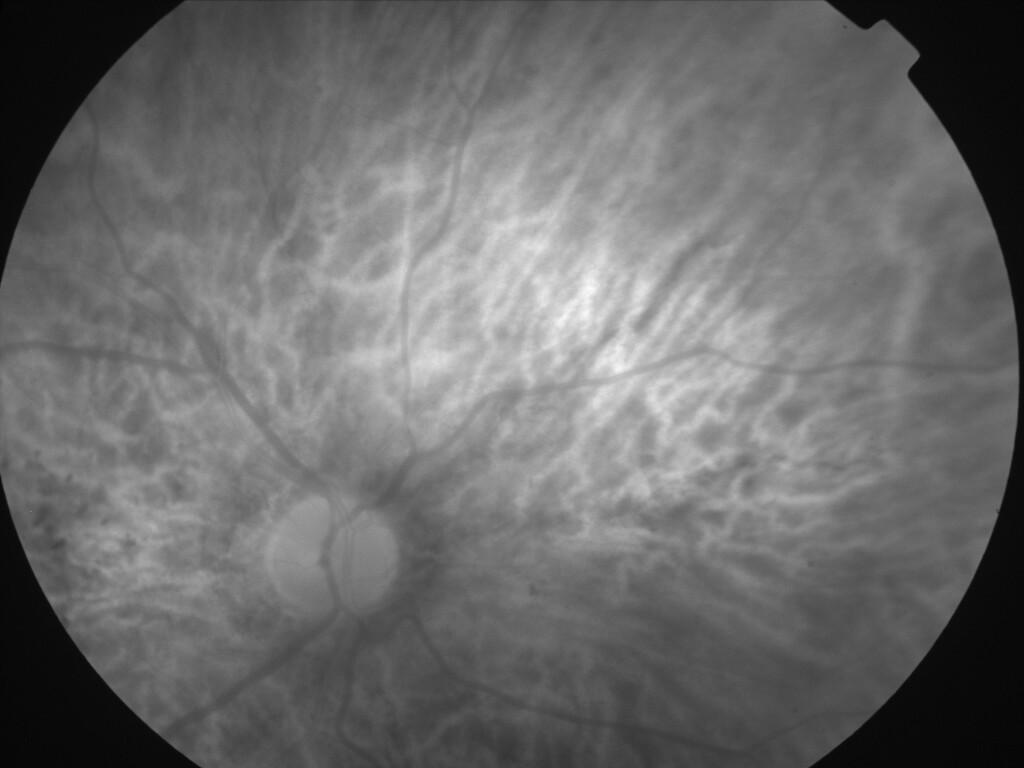

ASSOCIATION STRIES ANGIOIDES ET DYSROPHIE MACULAIRE RETICULEE

NEOVASCULARISATION